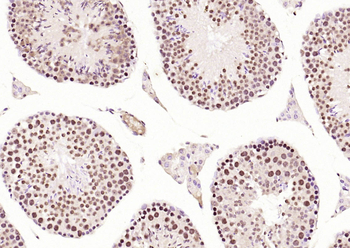

CDKN1A Antibody

Catalog Number: orb682382

| Description | CDKN1A Antibody |

| Target | CDKN1A |